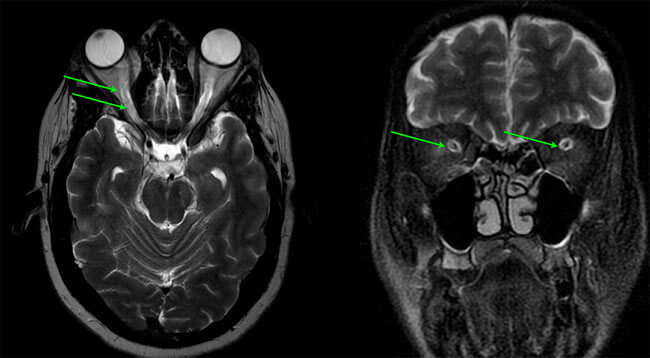

Os sinais e sintomas clínicos incluem cefaléia, zumbido pulsátil, papiledema, obscurecimentos visuais transitórios, perda visual, dor cervical, dorsalgia, e diplopia . Não há evidências de deformidade nem de obstrução do sistema ventricular, e os estudos neurodiagnósticos são normais, exceto pela pressão do líquido cefalorraquidiano (LCR) elevada e pelos sinais dos exames de neuroimagem relacionados( Ressonância Magnética Cerebral , AngioRessonância venosa, Ultrassonografia da bainha nervo óptico). Além disso, não há causa secundária aparente de hipertensão intracraniana.

Além disso, também é possível que o médico indique a realização de exames de tomografia ou ressonância magnética do crânio a fim de verificar que não há outras possíveis causas para o aumento da pressão interna do crânio, como trombose venosa cerebral.